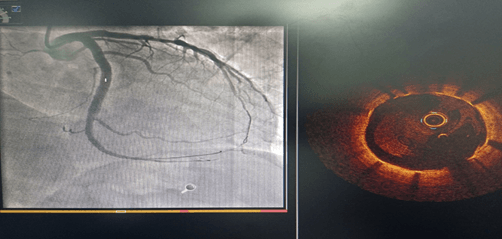

術(shù)前CAG示:LCX中段80%狹窄 ;OCT示纖維斑塊,最小管腔面積3.1mm2

術(shù)后OCT示:支架貼壁及膨脹良好,無夾層及血腫